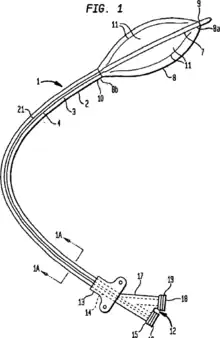

Ingemar Henry Lundquist invented the over-the-wire balloon catheter that is now used in the majority of angioplasty procedures in the world.[43]